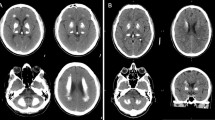

Primary familial brain calcification (PFBC), formerly known as Fahr’s disease or idiopathic basal ganglia calcification, is an inherited and intractable disorder mainly characterized by progressive bilateral calcification distributed in the basal ganglia region and/or other areas of the brain [7]. PFBC can serve as an ideal model in which to study the pathogenesis and potential prevention and treatment of brain calcification. PFBC can result in a variety of clinical symptoms, ranging from occasional migraines to serious symptoms including motor disorders (parkinsonism, tremor, and dystonia), cognitive disorders (memory impairment, executive dysfunction symptoms, and mental retardation), and neurological disorders (depression, affective disorder, and insanity), but nearly one-third of the carriers of causative gene mutation are asymptomatic [3, 8, 9]. Due to the high degree of clinical heterogeneity, the clinical symptoms are not suitable criteria for a diagnosis of PFBC. In contrast, the clinical diagnosis mainly relies on brain calcification identified by computed tomography (CT). The most typical feature in the neuroimages of PFBC patients is symmetrical bilateral calcification in the basal ganglia, thalamus, frontal cortex, or cerebellum. However, the levels of calcium (Ca), phosphorus (P), alkaline phosphatase, parathyroid hormone, and other serum biochemical indicators are normal in PFBC patients [3, 10, 11]. The overall prevalence of PFBC is estimated to be 0.21%–0.66% [12, 13].

It has been >170 years since the initial report of a case of bilateral basal ganglia calcification by Delacour in 1850 [14]. The genetic etiology of PFBC was largely unknown before the identification of SLC20A2 as the first associated gene in 2012 by Prof. Jing-Yu Liu’s lab [11]. A few pathological studies found that the main component of brain calcification is hydroxyapatite [15, 16]. Calcification particles mainly occur in adventitial vessel cells and sometimes in glial cells, as observed by transmission electron microscopy. Some spherical and hemispherical calcium deposits have been located in the vascular adventitia and connected to the filamentous processes of surrounding cells, as observed by scanning electron microscopy [17]. Furthermore, in some PFBC cases, large spherical calcification particles, mainly calcium phosphate, have been reported to be attached to the capillary wall and located in the media of some large arteries, and reactive astrocytes and microglia have been found to accumulate around the calcification sites [18, 19]. A few neurofibrillary tangles and dystrophic neurites in the medial temporal lobe, rarely spreading senile plaques, and a few amyloid deposits in vascular walls have been detected by silver staining and immunohistochemical staining [20]. Overall, these studies demonstrate that brain calcifications are mostly associated with blood vessels and sometimes involve neurons or glial cells, but the calcification process is still largely unknown.